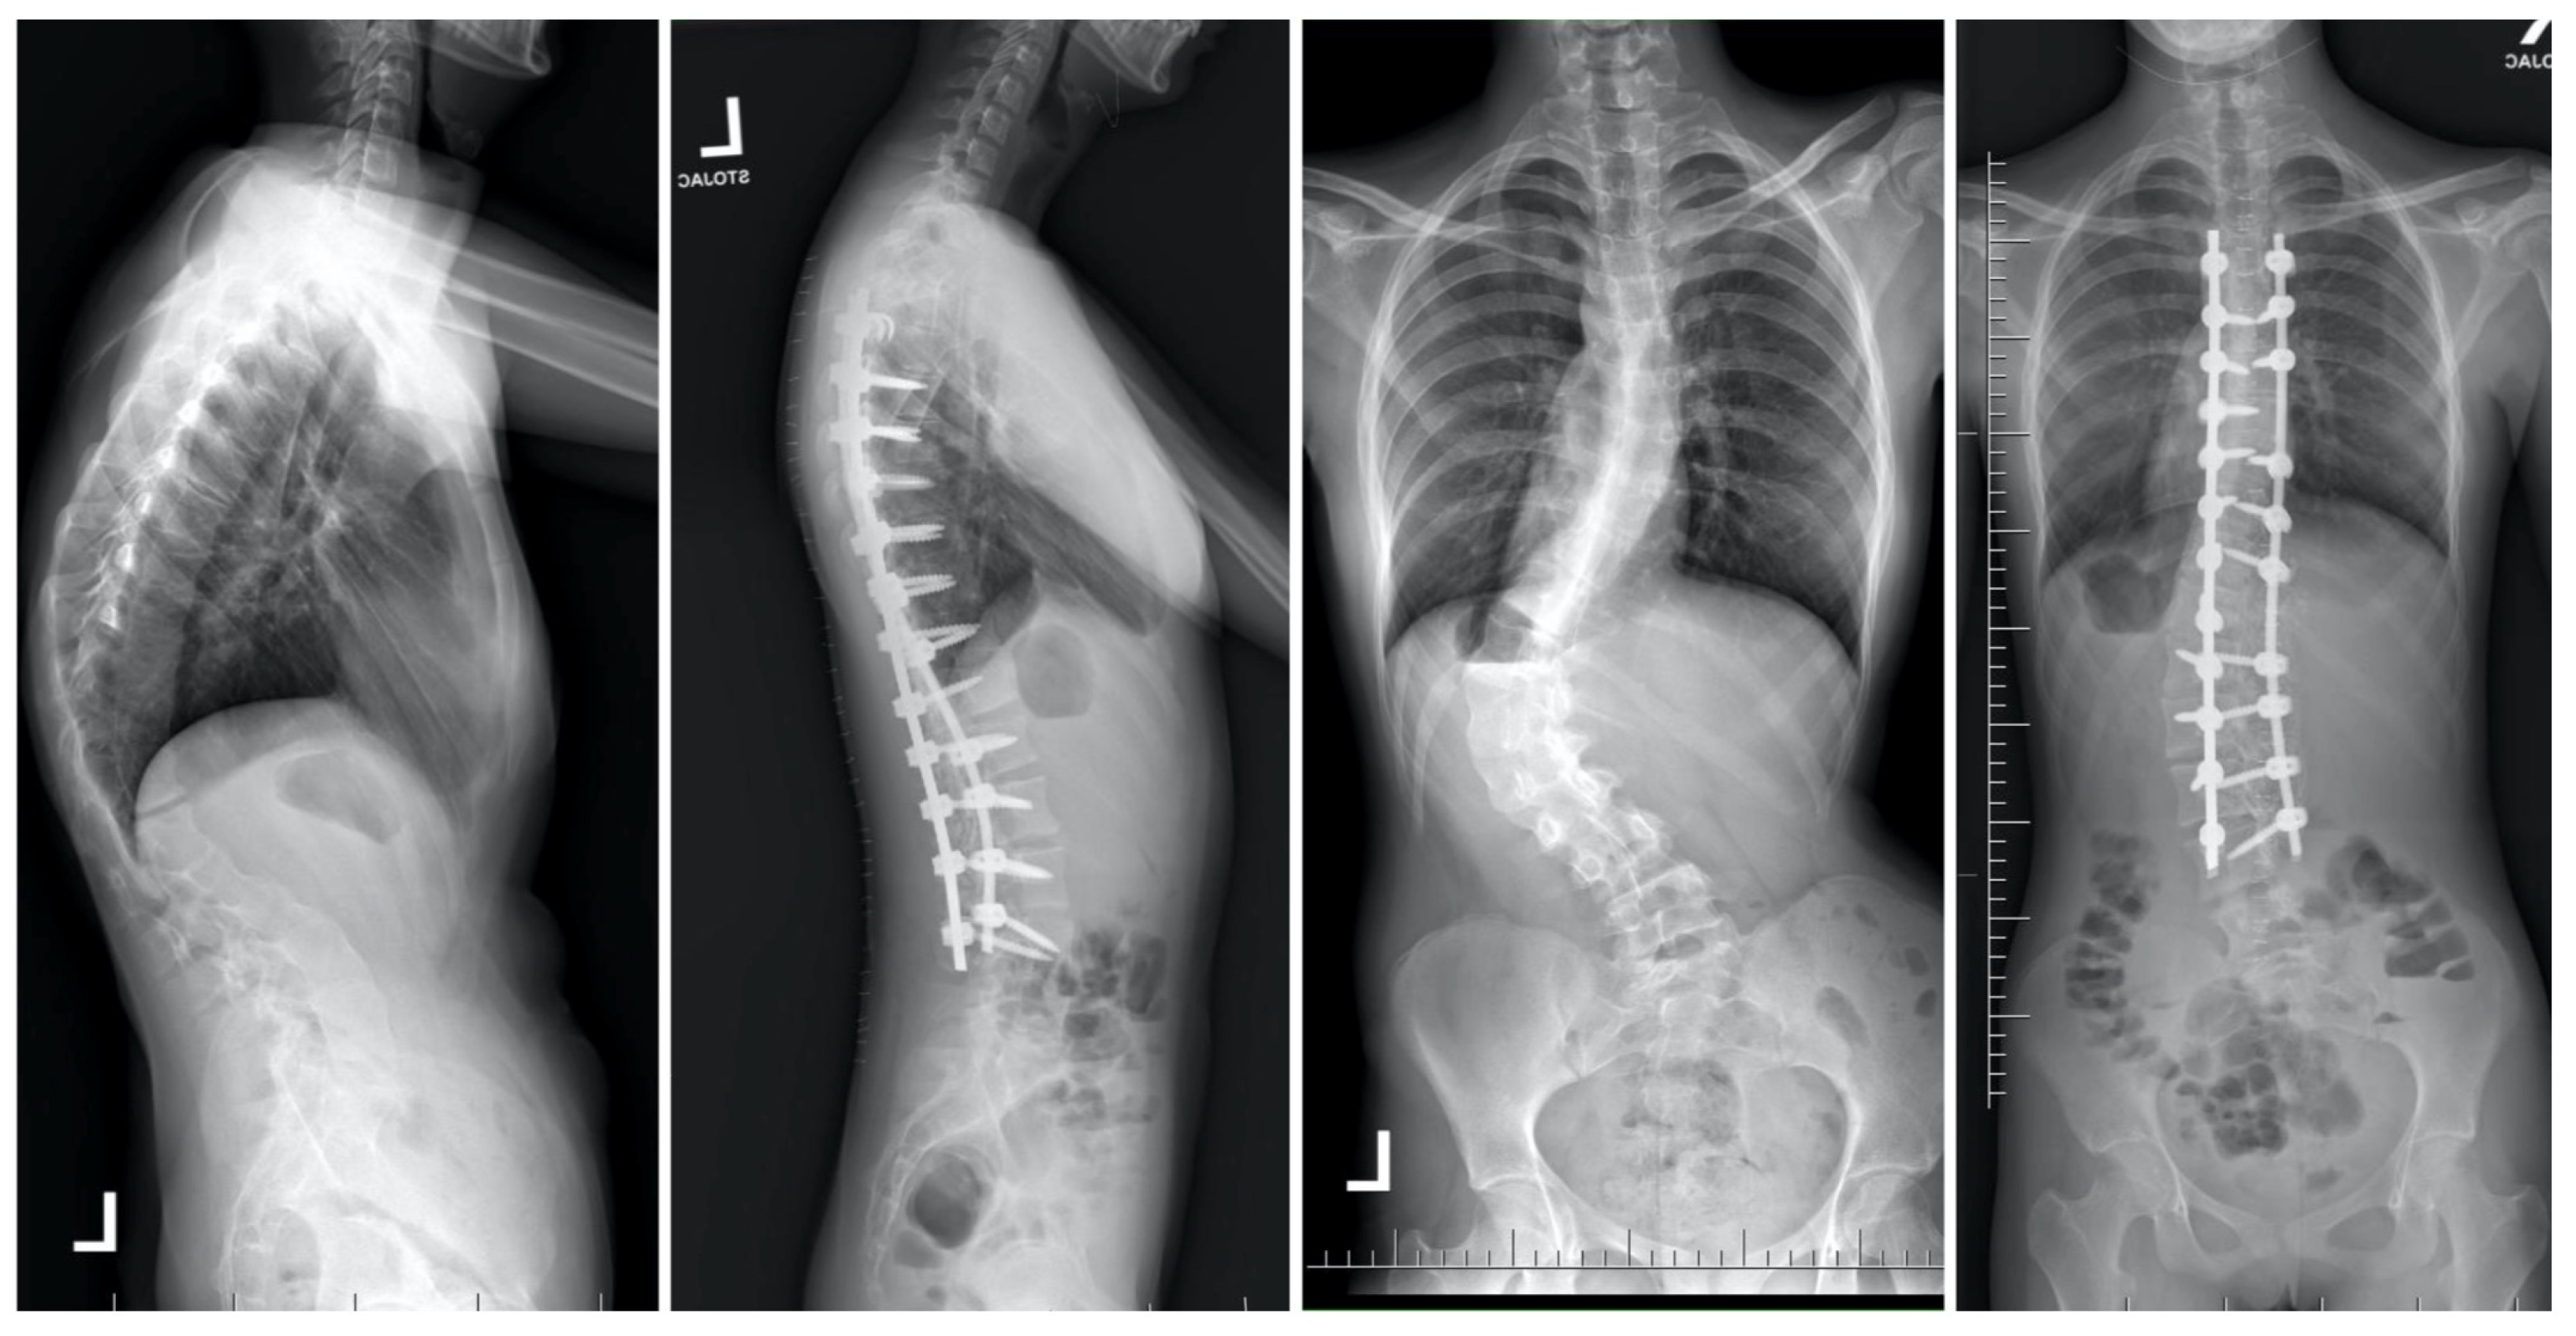

Temporary internal distraction (TID) involves the placement of fixation points at the top and bottom of rigid spinal curves, utilizing spinal instrumentation to distract the spine akin to methods employed in growing rod constructs [18,22,23,33,69,79,80,81,82,83]. Due to prolonged hospitalization and potential complications linked to HGT and hybrid fixation techniques (HFT), these options may not be suitable for all patients [44,84]. TID could serve as a viable alternative in cases where external traction is not recommended and can also be integrated into a single-stage procedure to complement other corrective interventions [18,23,82]. A study involving 10 patients with significant, inflexible curves, for whom HGT was unsuitable, revealed that 6 patients underwent an initial anterior release, while 4 did not [18]. All patients received temporary posterior distraction instrumentation and subsequently underwent definitive fusion surgery approximately 2.4 weeks later. During treatment, six patients underwent multiple distraction procedures [18]. Buchowski et al. observed an average curve correction of 53% (ranging from 39% to 79%), exceeding the pre-traction bending radiograph correction and yielding comparable results to HGT and HFT [83,84,85,86]. The study reported no instances of neurologic or infectious complications [18]. In a separate investigation encompassing eleven patients afflicted with severe and inflexible scoliosis who underwent treatment with TID, Hu and colleagues documented a notable 53% amelioration in the major Cobb angle, concomitant with an enhancement in forced expiratory volume in 1 s from 61.4% to 71.3% [79]. Furthermore, the scholars observed the conspicuous absence of any neurologic or infectious complications arising from the procedure. The methodology employed for TID closely mirrors the technique delineated by Buchowski and colleagues [18,23], albeit with certain modifications, as elucidated in the existing literature [22,23,33,69,80,81,82,83]. The conventional prone positioning is utilized, consistent with the approach for any intervention involving the posterior aspect of the spine. The integration of neuromonitoring stands as a pivotal and indispensable phase, particularly throughout the distraction process. The initial stride entails effectuating a midline incision in the skin, succeeded by subperiosteal dissection to expose the requisite anchor points. For the cephalad fixation, either infralaminar or subpedicle hooks are situated. It is imperative to circumvent sitting these hooks at the designated levels for ultimate fusion to avert potential bone impairment. Additionally, cephalad anchor points might encompass the ribs. Typical caudal anchor points include down-going laminar hooks, lumbar pedicle screws at adjacent levels, or attachment to the pelvis. These anchor points frequently slacken during the distraction phase and should not function as ultimate anchor points for fusion. If iliac screws are employed, they should be positioned to accommodate the insertion of new screws just distal to them during the definitive procedure. Diverse rod constructs can be utilized, with the most elementary one comprising a rod for cephalad anchors and another for caudal anchors interconnected by a side-to-side connector. Subsequent to the placement of rods and the execution of distraction, extensive posterior releases are executed at each rigid deformity level. Gradual increments in distraction are subsequently applied to harness the viscoelastic characteristics of the spine and attain maximal distraction. The surgical incision is sutured according to the surgeon’s preference, and patients are mobilized postoperatively sans the necessity for bracing or casting [22,86]. Ordinarily, a minimum of one week of TID is permitted before definitive fusion is undertaken. Prolonging the distraction period beyond that is feasible but is improbable to yield enhanced correction. Throughout the definitive fusion, the provisional implant is extracted, and the ultimate instrumentation is introduced. TID can also be conducted in a single-stage modality. The distraction construct is positioned early in the procedure to instigate distraction, while other facets of the surgery are finalized. The construct can subsequently be gradually elongated until the final instrumentation is in situ. Subsequently, the TID construct is eliminated before closure, obviating the necessity for a subsequent procedure [22]. Hu et al. propounded an alternative strategy for treating thoracolumbar idiopathic scoliosis, entailing minimally invasive incisions specifically at the requisite anchoring levels [79]. Unlike other methods, the authors did not carry out sub-periosteal dissection. Their technique involved placing two pedicle screws at the top and bottom levels of the primary Cobb angle, connecting them with rods and a side-to-side crosslink. The authors advised post-operative orthosis use and allowed a distraction period of up to 15 weeks before proceeding with definitive fusion [22,79]. Figure 10 presents a 17-year-old female patient underwent a staged surgical treatment involving the less invasive temporary internal distraction technique followed by posterior spinal fusion.

Figure 10.

A 17-year-old female patient underwent a series of surgical procedures involving the less invasive temporary internal distraction technique followed by posterior spinal fusion. Radiographs were conducted before the initial stage, after the first stage, and post-operatively during the final follow-up.